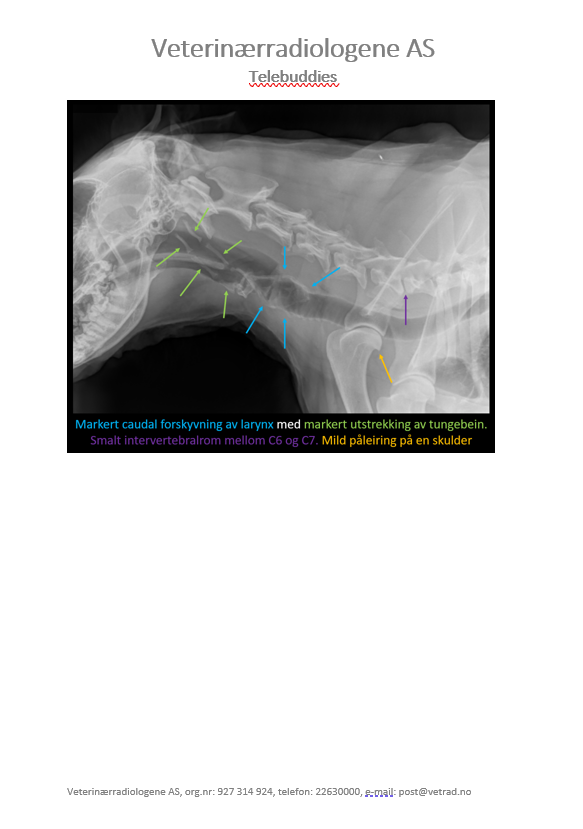

Denne gangen har vi lyst til å dele et kasus som vi syns er ganske interessant. Studien ble sendt inn til oss fra Dyrlegene i Skolestua, og sammen kom vi frem til en diagnose som kan forklare hundens problemer. Signalement: Pyreneerhund, tispe, 9år Anamnese: Eier syns hunden har blitt i dårligere form over tid, den bruker lang tid på å spise, tiltagende hosting. Eier har sau, så hunden jobber som vokterhund. Etter anstrengelse bruker hunden lang tid på restitusjon, peser lenge.